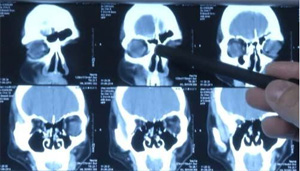

陈主任建议小罗带着妹妹经过鼻部CT以及3D超频点位可视镜检测,经过科学规范化诊疗,陈主任发现小罗妹妹已经是鼻窦炎双侧炎症并发鼻炎,加上之前的盲目诊疗药物服用有转化药物性鼻窦炎趋势,后期治疗难度有所增加。

CT检查结果